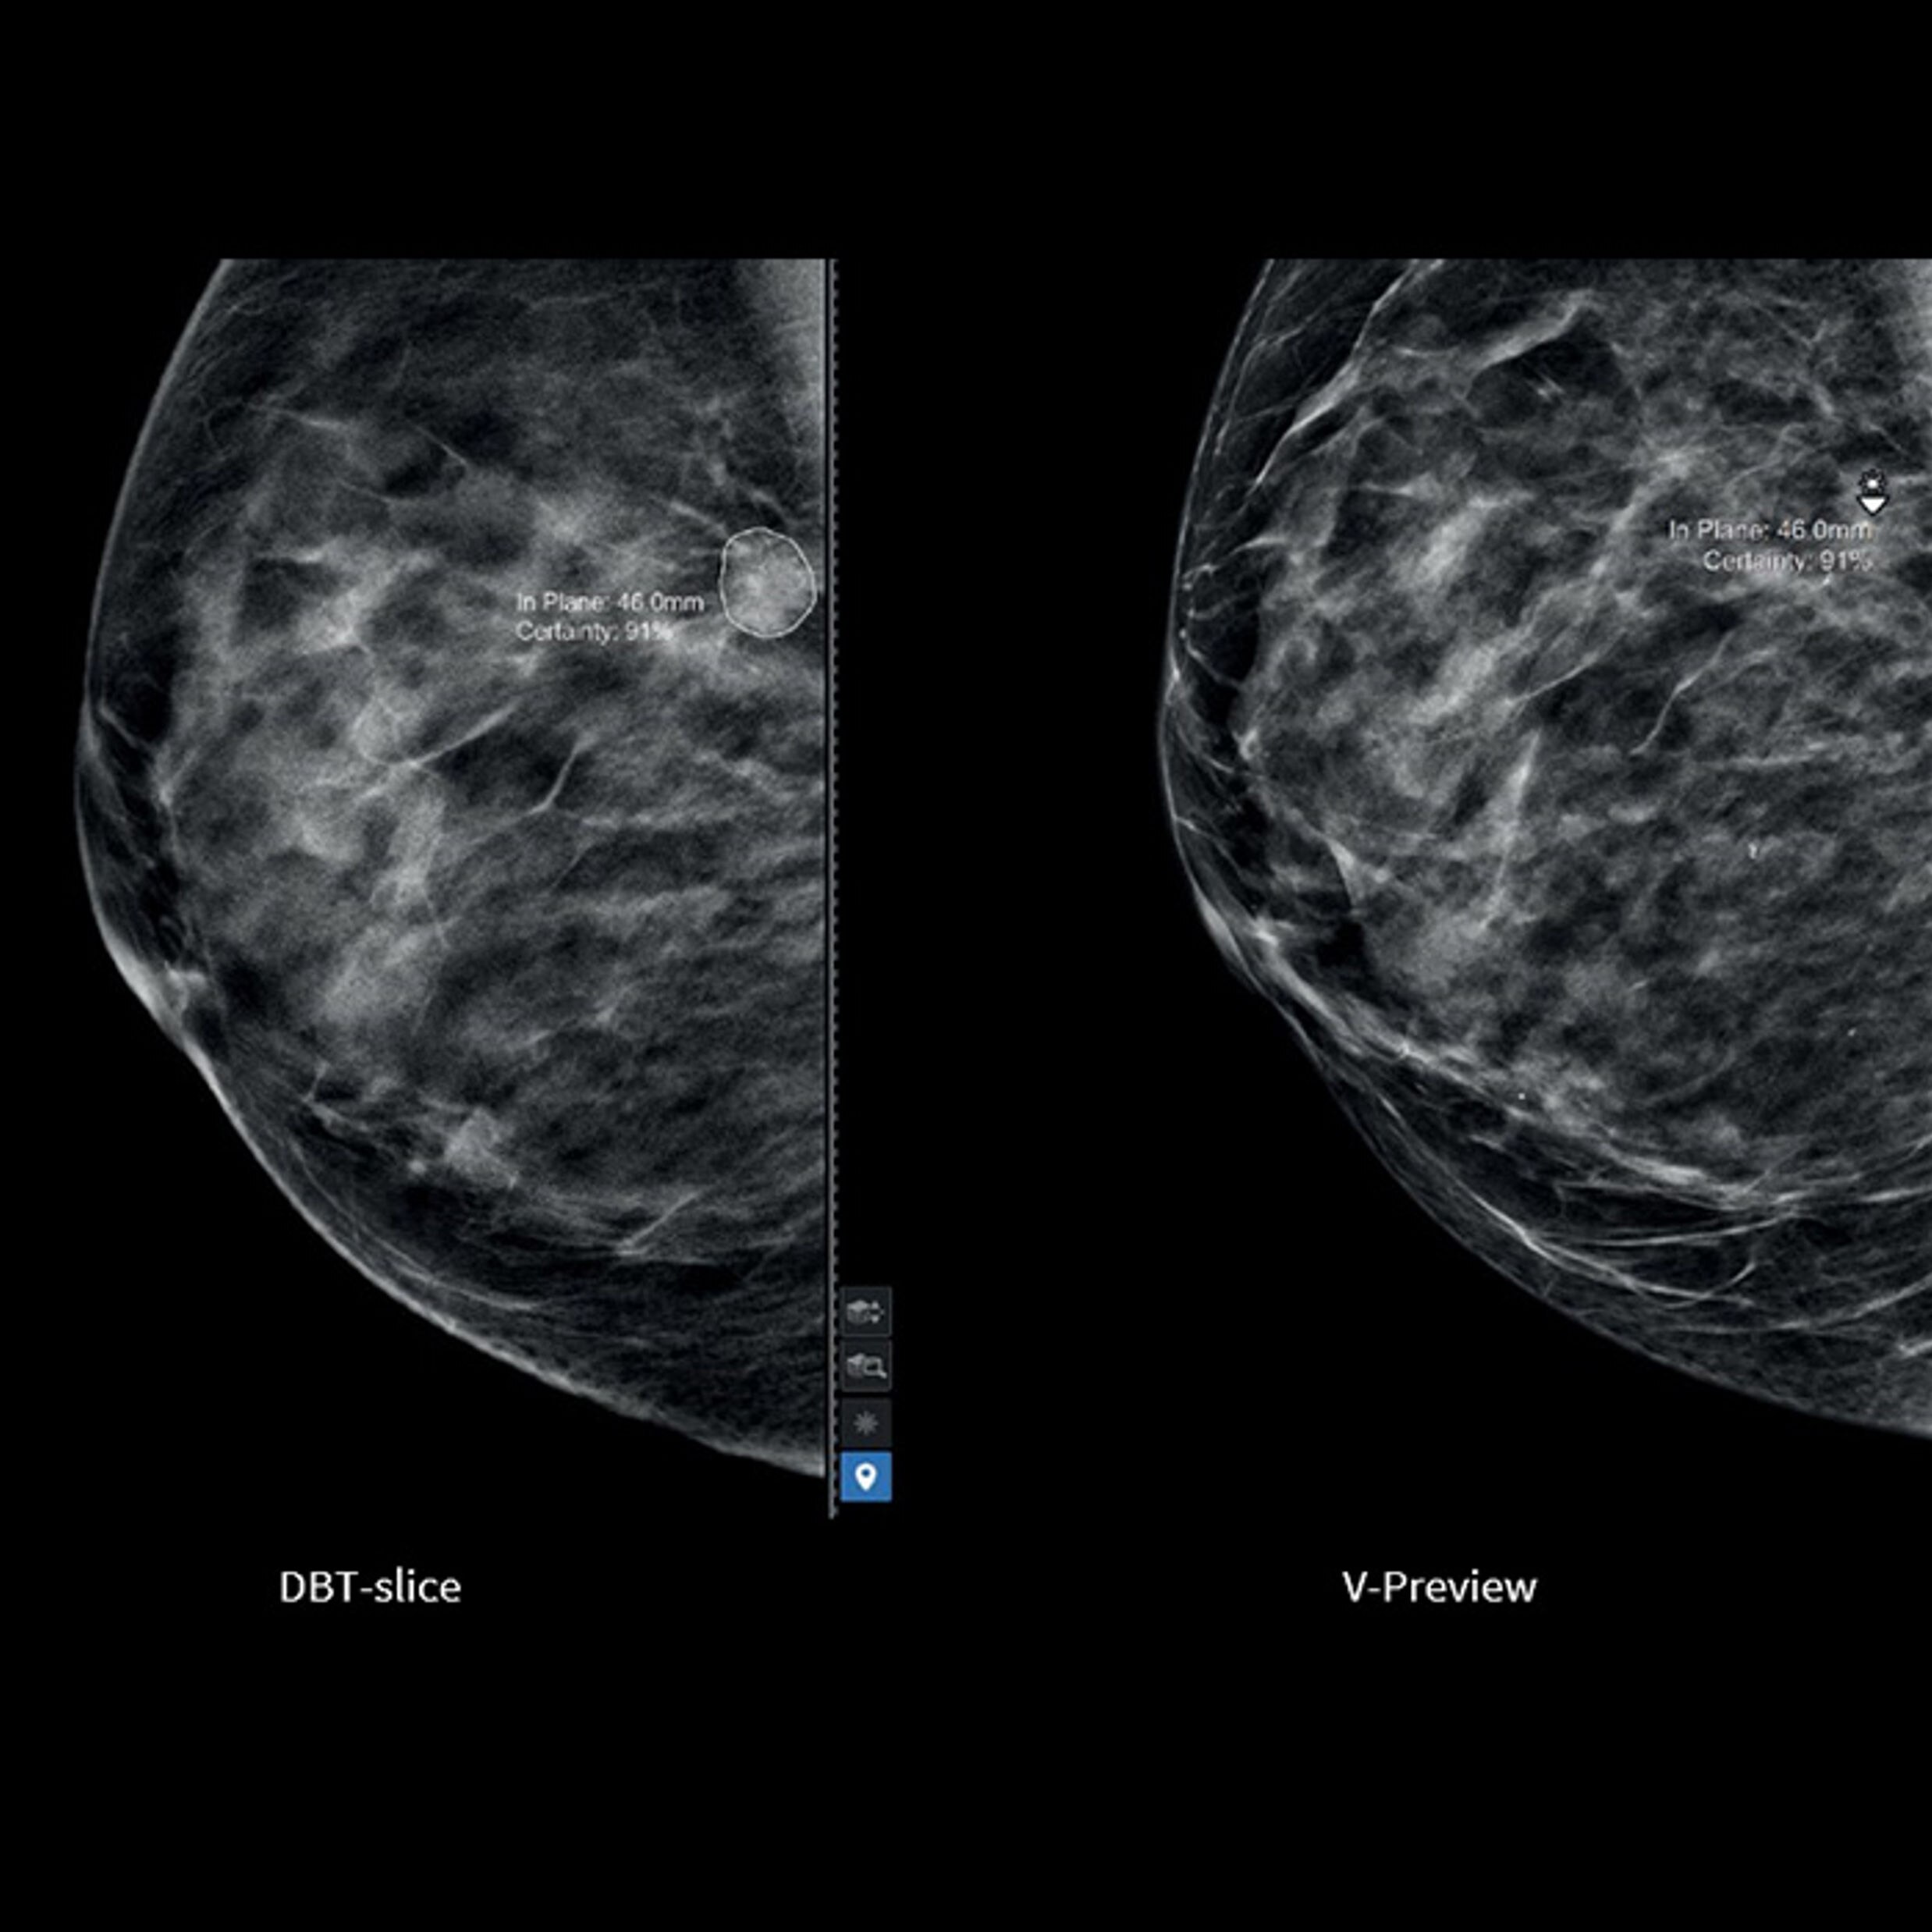

Follow nerve block procedures with cNerve

Helps detect and track nerves in 99% of cases during live scanning or while reviewing a stored clip2 while also displaying a distribution map of the areas on the body impacted by the selected nerve block procedure.